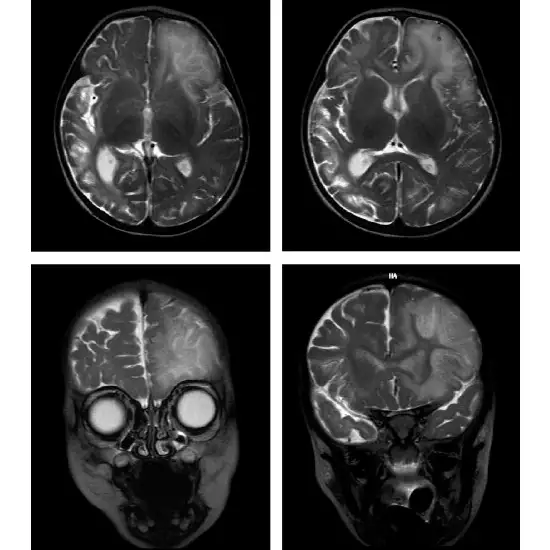

The condition hyperornithinemia-hyperammonemia-homocitrullinuria syndrome (HHH) occurs when the body is unable to process and eliminate ammonia. Because ammonia is produced when the body breaks down proteins in food into their basic building blocks, it is considered an amino acid condition (amino acids). When the body's waste removal process is disrupted, dangerous levels of ammonia begin to accumulate in the blood. If untreated, this can lead to developmental delays, learning disabilities, or stiffness caused by abnormal muscle tensing (spasticity).

HHH syndrome is an autosomal recessive disorder caused by a defect in Urea cycle metabolism. It can appear at birth, during childhood, or even in adulthood.